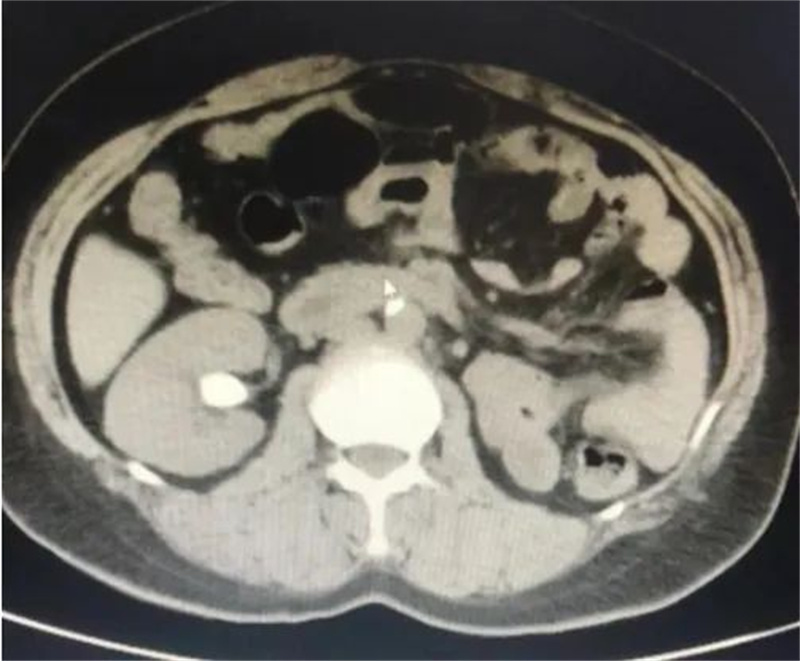

泌尿外科新技术治疗上尿路结石,安全高效碎石清石